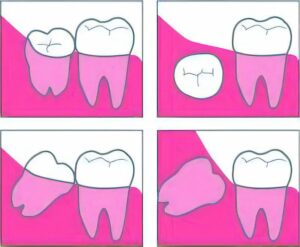

智歯(親知らず)は、全ての歯の中で一番最後に生え、第二大臼歯の後方(一番奥)に生えます。しかし正常に生えることができず、斜めに生えたり、顎の中に生えずに残ってしまうことがあります。

重度の虫歯や、智歯周囲炎、第二大臼歯の虫歯や歯周病の治療のために抜歯が必要になる場合があります。

智歯の抜歯は、生え方にもよりますが、歯肉の切開したり歯牙を分割するなど特殊な抜き方が必要なこともあるため、”親知らずを抜きたくても不安のある方”、“口腔外科医の診察を希望の方”は、ご相談ください。